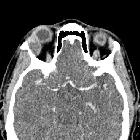

CT

Axial and coronal CT shows peripheral and mild central heterogeneous enhancement.